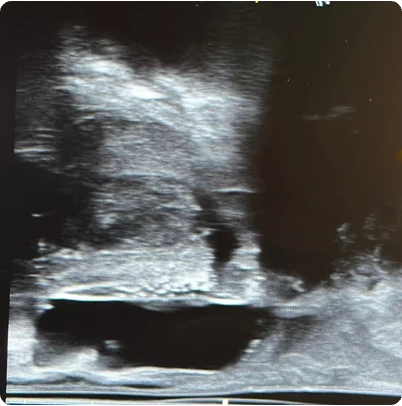

169 cc prostate ultrasound saggital view showing BioProtect Balloon Spacer, prostate, and rectum.

Saggital Ultrasound

Image courtesy of of Dr. Vishesh Agarwal, Radiation Oncologist.